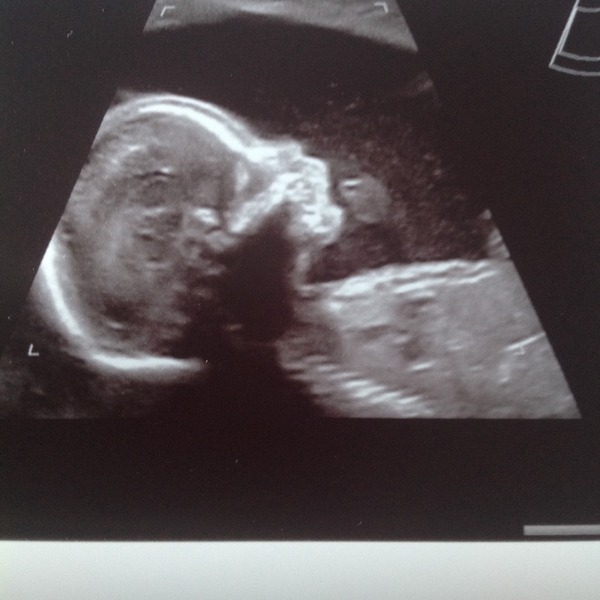

Well, had the scan yesterday and got some very cute photos, which I am attaching - one of his little foot, which is apparently 3cm long already! And he is definitely a boy!

His measurements are all spot on, and mostly his organs look good, but they were a bit concerned about his bowel which looked 'a bit bright' around the edges on the screen, so I am being referred to a consultant at the FMU.

They asked if I'd had any bleeding, as apparently the baby can ingest blood in the amniotic fluid which can make the bowel look bright, but I've not had any bleeding all pregnancy as far as I know (tho DH did point out that all my knickers are black - but I have checked every time I've wiped since October.) They said it was borderline whether or not it was actually a problem, but they would rather be over-cautious. However, they said lots of the doctors are on holiday next week because of half term, so god knows how long I will have to wait to be seen.

Bluebel those are lovely pics. Please don't talk to Dr Google. He always has the worst prognosis. Go with the professional assurances that all is ok.

They are beautiful photos!! I agree, never look up on google because it'll say so many different problems and you'll worry yourself silly! Im sure baby is okay Smile